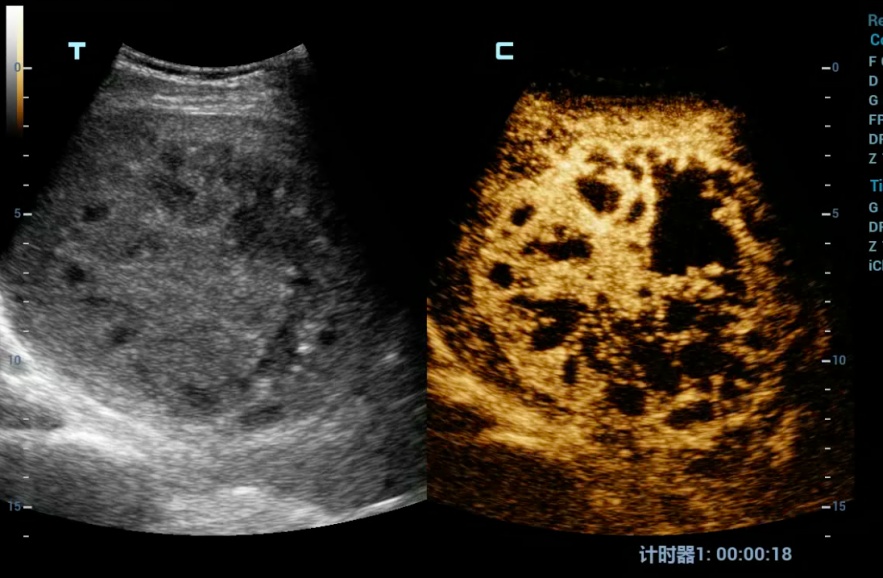

术前对病灶进行充分评估,并做了超声造影,肝脓肿较成人拳头略大,內见较多的分隔。

于是,我们决定进行肝脓肿的置管引流。同时,患者的核酸报告结果也为阴性,在封控的情况下,我们第一次在身穿防护服及三层手套的条件下进行手术,抽出脓液20ml,并顺利完成了置管引流,过程顺利,病人安全。

此项技术是指通过超声评估,确定患者是否满足肝脓肿穿刺的条件、有无进针的安全路径以规避肝内重要管道结构(如肝动脉、肝静脉、肝内胆管及门静脉等)。患者通常局部麻醉,在超声实时监测下,医生可从入皮肤开始,全程直观的观察并操作穿刺针以最安全的路径到达肝脓肿部位,抽吸脓液并置管引流,具有安全、创伤小等优点。